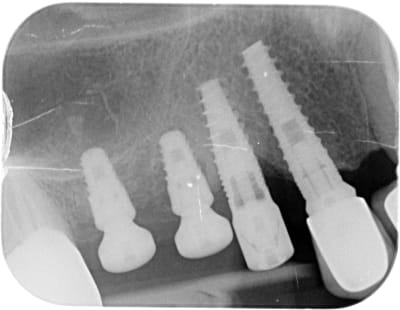

Quelqu'un saurait-il m'indiquer la marque de l'implant en 14 SVP, celui avec le pilier de cicatrisation?

çà ressemble à de l'IDI

https://www.spotimplant.com/fr/implants-dentaire/idi-dental/id-bio

Si tu regardes bien la radio….amha il y a un multiunit dessus avec une vis de confort….